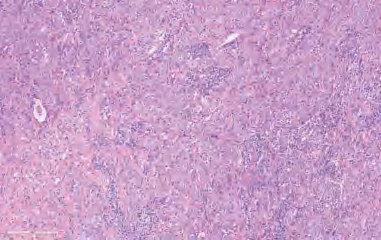

【镜下形态】LCC由大的多角形细胞成片组成或呈巢状,肿瘤细胞核呈泡状,核仁明显,细胞质中等(图2-11)。可能存在透明细胞或横纹肌样细胞特征。在通过免疫组织化学排除小细胞癌、腺癌、SCC和巨细胞癌、梭形细胞癌或多形性癌及其他转移性癌后,才能作出LCC诊断。TTF-1和p40是检测腺癌或鳞状细胞分化的首选免疫组织化学标志物。若二者为阴性,还需检测黏液染色为阴性或<5个阳性细胞/2个HPF(0.4 mm 2 ),以排除含黏液的实性腺癌。如果TTF-1和p40阴性,则不建议使用NapsinA和CK5/6来检测腺癌和鳞状细胞的分化。根据需要,还应进行CK染色,以确认上皮分化。TTF-1和p40阴性的病例应称为“LCC(裸免疫表型)”。依靠有无神经内分泌形态学特征以及免疫组织化学神经内分泌标志物(嗜铬粒蛋白、突触素或CD56)可与大细胞神经内分泌癌相鉴别。对于缺乏神经内分泌形态的病例,不建议使用神经内分泌标志物。然而,如果组织形态学显示为未分化的非小细胞癌且CK和NE标志物表达呈阳性,TTF-1和p40表达呈阴性,则应称为“具有NE分化的LCC(或具有NE免疫表型的LCC)”。横纹肌样细胞有时增加了癌肉瘤伴横纹肌肉瘤分化区域的可能性,但是具有横纹肌样细胞学的LCC,其细胞角蛋白是阳性的,desmin和myogenin是阴性的。在类似LCC的肿瘤中出现横纹肌样形态,应考虑SMARCA4基因缺失的胸部肉瘤样肿瘤的可能。肿瘤显示超过10%的多形性特征(梭形或巨细胞)应归类为多形性癌。为了排除胸外的低分化癌、淋巴瘤、恶性黑色素瘤或间皮瘤等转移性肿瘤,通常需要再根据细胞角蛋白和其他部位肿瘤的免疫组织化学标记,结合临床-放射学相关检查资料综合判断。LCC需要对手术切除的肿瘤进行彻底取样后才能作出诊断,非手术的小活检标本或细胞学标本检查不能直接作出诊断。

图2-11 LCC